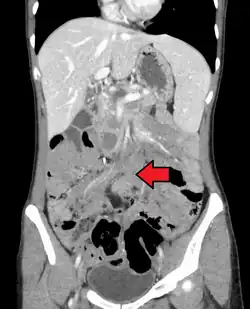

| Desmoid tumor as seen on CT scan | |

MRI or CT imaging scans are commonly used for monitoring.[47][1]